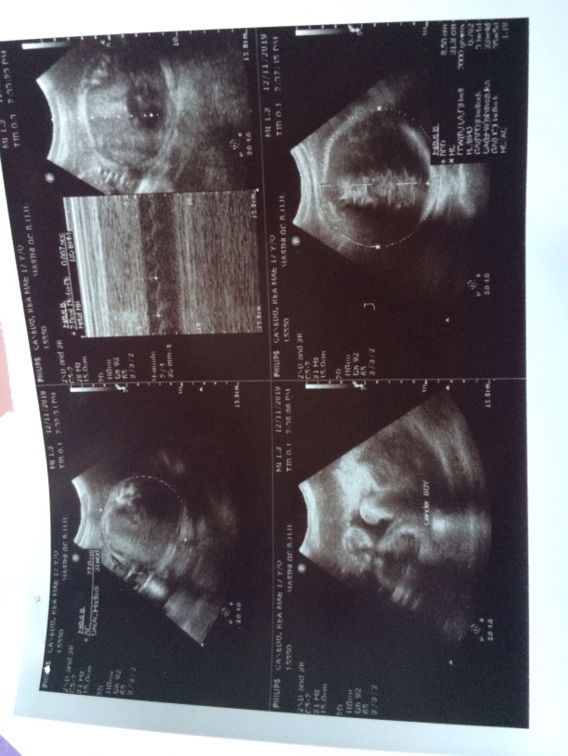

By my 1st ultrasound twin baby girl ang result pero kanina nung pag 2nd ultrasound ko Boy&Girl na ? . Sobrang nakakagulat dahil ok na sana mga gamit pero puro pang baby girl ang napamili ? . Currently 8months pregnant . Team January❤️

Ilang weeks kapo nung unang nagpautz for gender? Ako po kasi 20weeks and 4days both baby girls din e. Di po ba pinakita sayo yung hiwa ng baby mo?